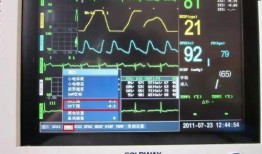

心电监护仪的操作视频,轻松掌握生命体征监测技巧

你有没有想过,在医院里,那些躺在病床上的人,他们的心跳声是如何被医生们时刻关注的呢?没错,就是靠那神奇的设备——心电监护仪。今天...

2025-08-21 839